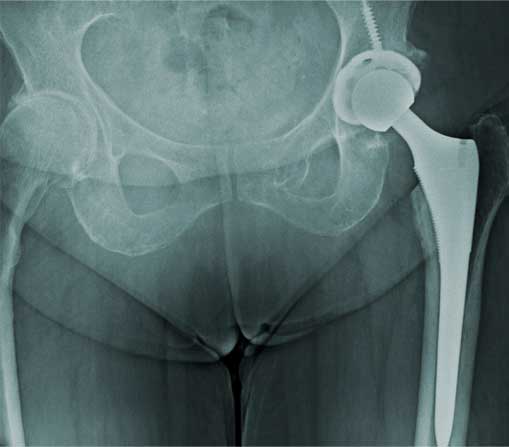

Prótesis de cadera

Es también conocida como reemplazo de cadera, la cual consiste en la sustitución de la articulación dañada o un implante de metal, cerámica o plástico que realiza la función de la articulación, mejorando el dolor.

¿Por qué se realiza?

Las indicaciones más comunes son la artrosis o desgaste de cadera en adultos mayores, otras indicaciones son las fracturas de cadera, el daño crónico o infección, artritis reumatoide, secuelas de enfermedades de la cadera o traumatismos, las cuales se presentan en adultos jóvenes y adultos mayores.

El paciente puede caminar desde el mismo día de la cirugía, se da de alta a su domicilio a las 24 horas y puede realizar actividades cotidianas en casa de forma autónoma desde la primera semana. La recuperación parte en un 80% de la función de la cadera en el primer mes, 90% de la función en el segundo mes y 92% - 98% de la función en el tercer mes.

Resultados esperados

Eliminar el dolor en la zona afectada, mejorar la función como es fuerza muscular, movimiento, estbilidad y biomecánica, logrando mejorar la calidad de vida del paciente.